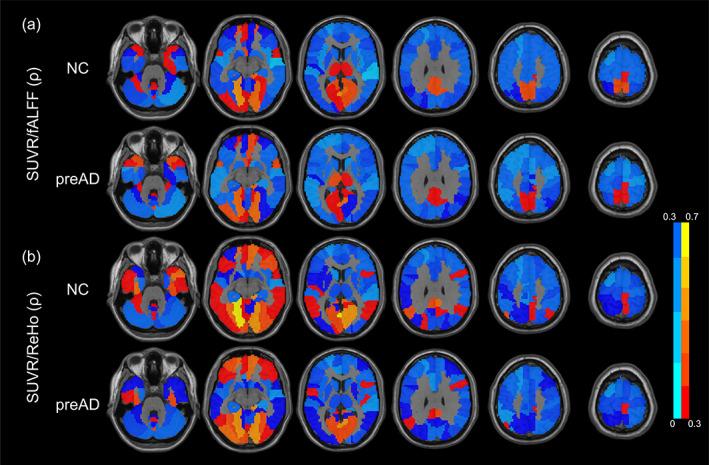

The discovery of preclinical Alzheimer's disease (preAD) provides a wide time window for the early intervention of AD. The coupling relationships between glucose and oxygen metabolisms from hybrid PET/MRI can provide complementary information on the brain's physiological state for preAD. In this study, we purpose to explore the change of coupling relationship among 27 normal controls (NCs), 20 preADs, and 15 cognitive impairments (CIs). For each subject, we calculated the Spearman partial correlation between the fractional amplitude of low-frequency fluctuations (fALFF) and the regional homogeneity (ReHo) from functional image (fMRI), and the standard uptake value ratio (SUVR) from [18F] fluorodeoxyglucose positron emission tomography ( F-FDG PET), in the whole-brain and default mode network (DMN) as a novel potential biomarker. The diagnostic performance of this biomarker was evaluated by the receiver operating characteristic analysis. Significant Spearman correlations between the FDG SUVR and the fALFF/ReHo were found in 98% of subjects. For the DMN-based biomarker, there was a significant decreasing trend for the preAD and CI groups compared to the NC group, whereas no significant difference in preAD based on whole-brain. The correlation ρ value for the FDG SUVR/ReHo showed the highest area under curve of the preAD classification (0.787). The results imply the coupling relationship changed during the preAD stage in the DMN area.

临床前阿尔茨海默病(preAD)的发现为 AD 的早期干预提供了广泛的时间窗口。杂交 PET/MRI 的葡萄糖和氧代谢的耦合关系可为 preAD 大脑的生理状态提供补充信息。在这项研究中,我们旨在探索 27 名正常对照(NC)、20 名 preAD 和 15 名认知障碍(CI)患者之间耦合关系的变化。对于每个受试者,我们计算了功能图像(fMRI)中低频振幅(fALFF)和局部一致性(ReHo)与 [18F]氟脱氧葡萄糖正电子发射断层扫描(F-FDG PET)中标准摄取值比(SUVR)之间的 Spearman 偏相关,作为一种新的潜在生物标志物,在全脑和默认模式网络(DMN)中进行。通过接收者操作特征分析评估了该生物标志物的诊断性能。在 98%的受试者中,FDG SUVR 与 fALFF/ReHo 之间存在显著的 Spearman 相关性。对于基于 DMN 的生物标志物,与 NC 组相比,preAD 和 CI 组表现出明显的下降趋势,而在全脑水平上,preAD 之间没有显著差异。FDG SUVR/ReHo 的相关 ρ 值显示了 preAD 分类的最高曲线下面积(0.787)。结果表明,在 DMN 区域,preAD 阶段的耦合关系发生了变化。